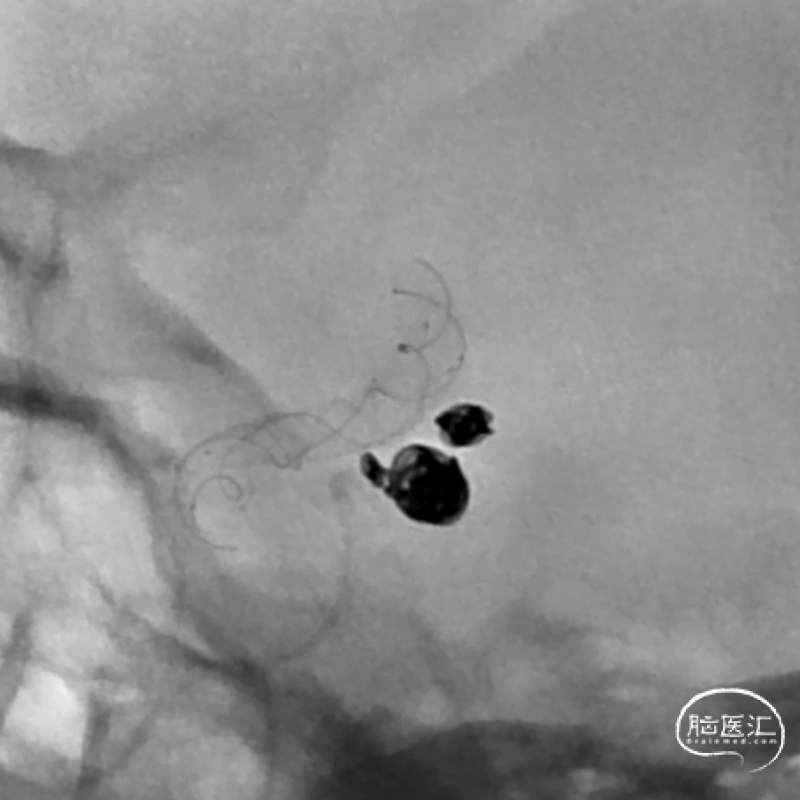

这是一根通桥银蛇DA远端通路导引导管,在Sim II和导丝到位后,通桥银蛇DA远端通路导引导管能够非常容易地顺着架设的道路直接放到位,然后进行后续使用Pipeline血流导向密网支架来治疗复发动脉瘤的操作。我们可以看到在Pipeline的到位以及释放的过程中,通桥银蛇DA远端通路导引导管都非常稳定,能够获得比较满意的结果。

释放PED过程中,通桥银蛇DA远端通路导引导管头端非常稳定。

术前

术后